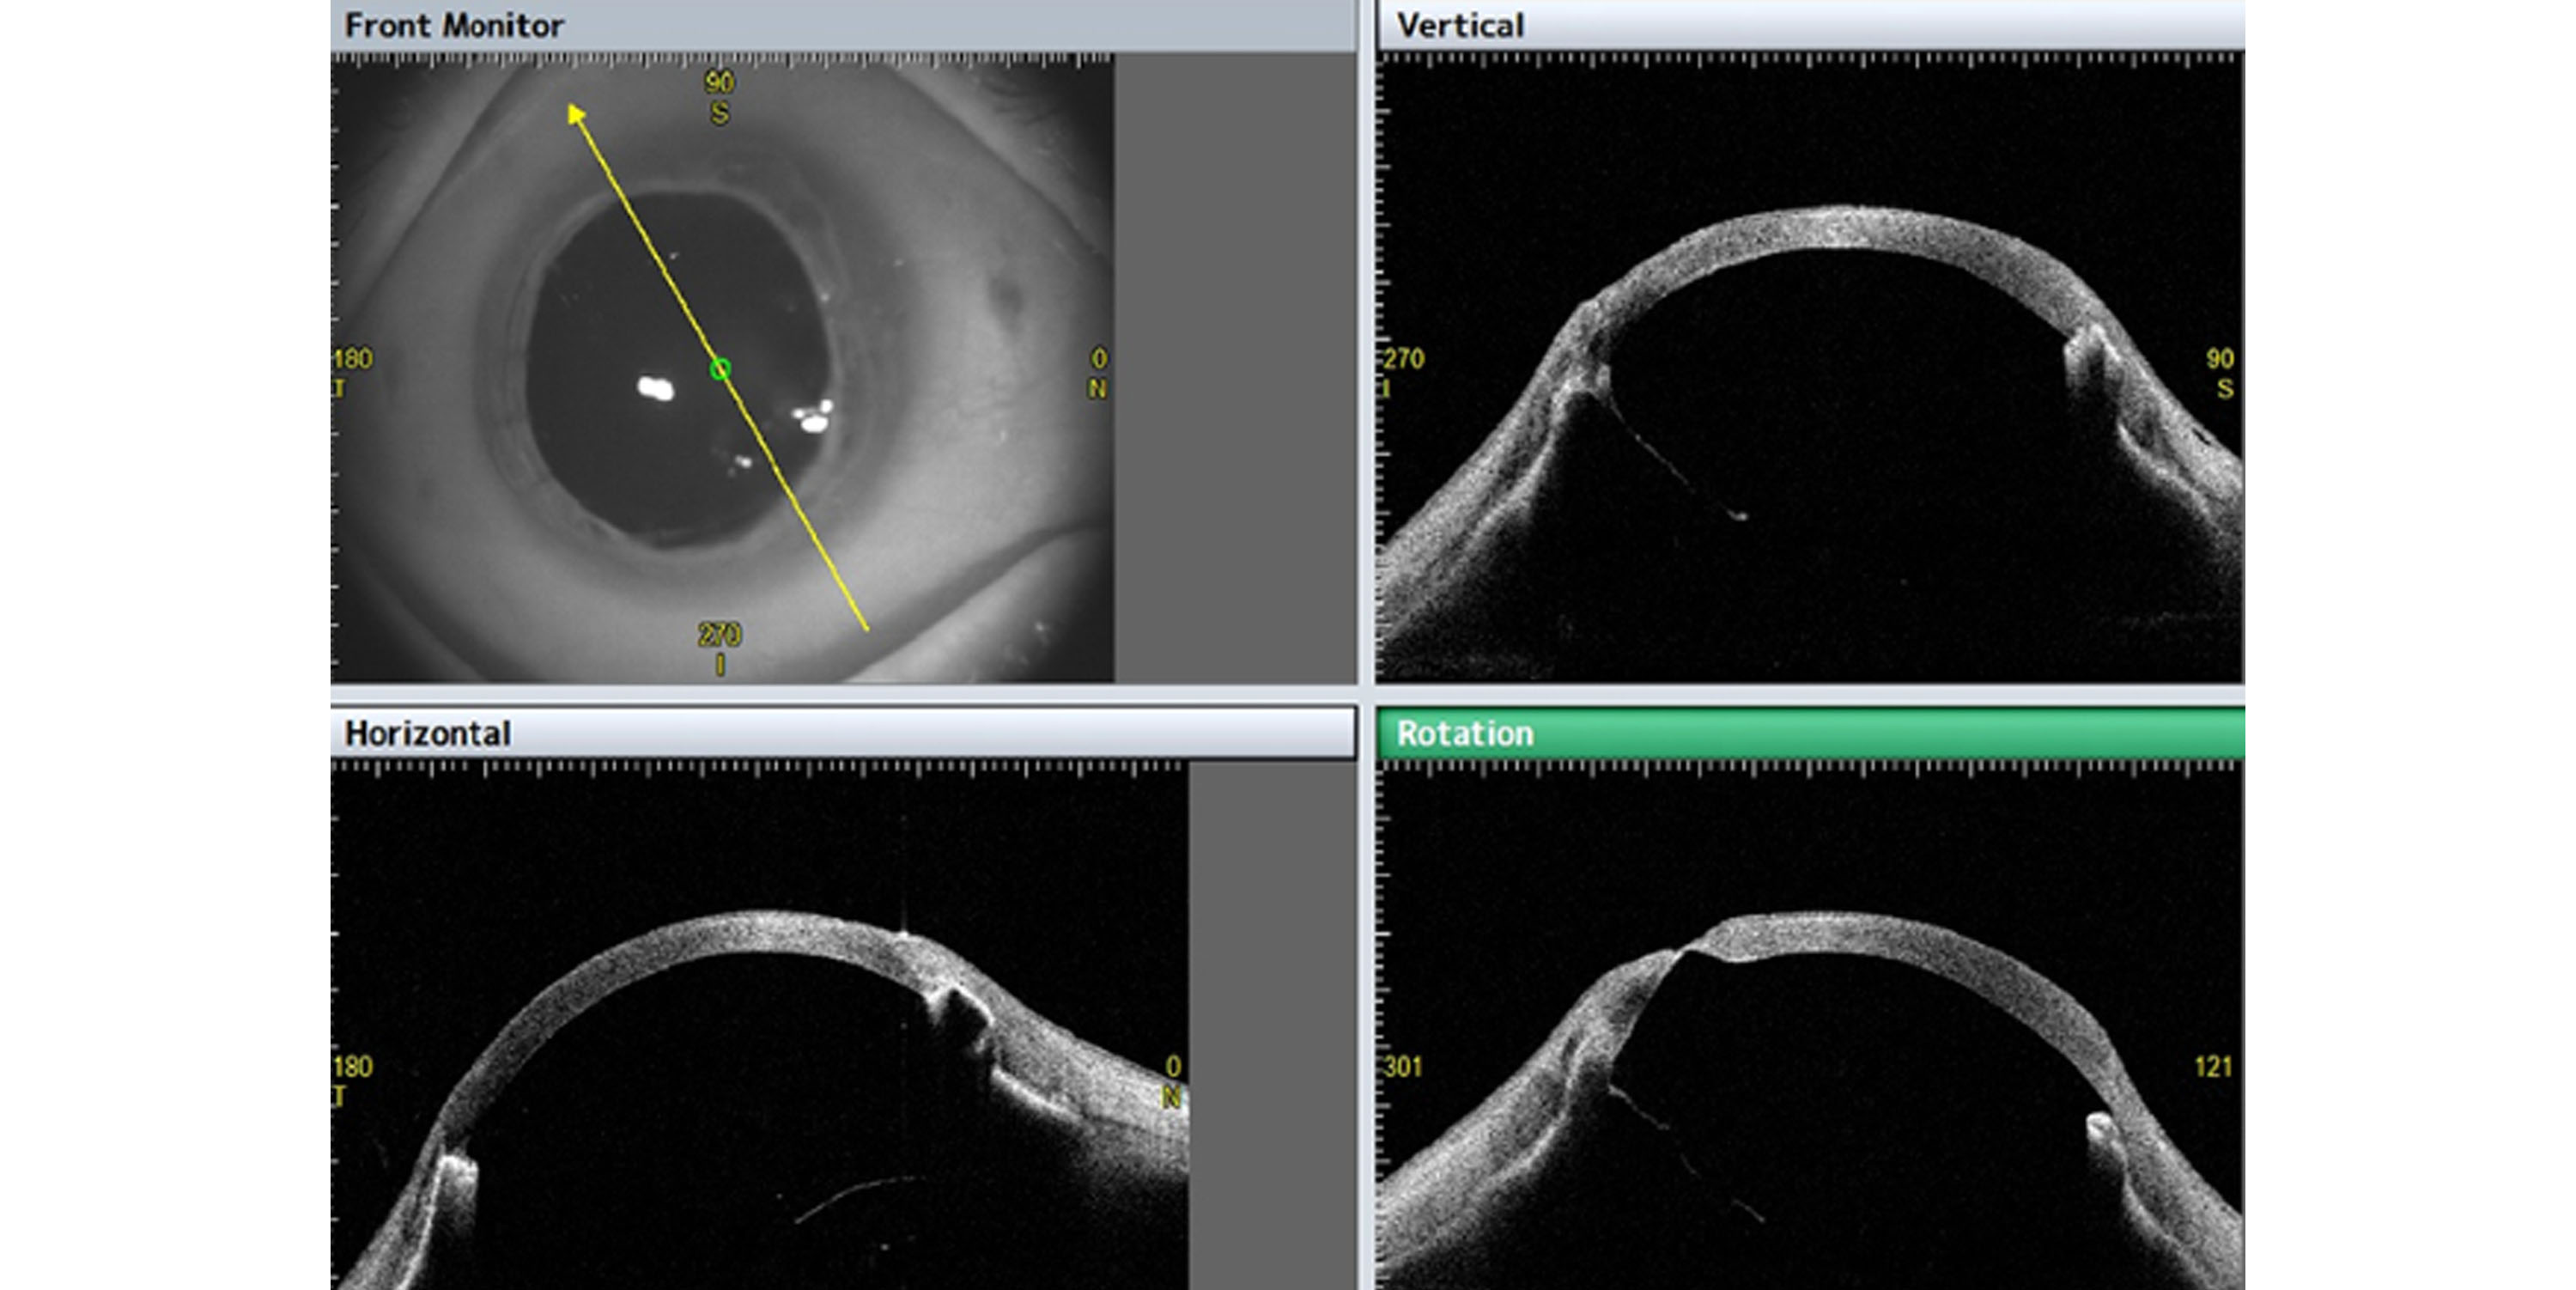

Designed for comprehensive corneal and anterior segment analysis, the CASIA 2 system from Tomey features a high-speed swept-source OCT engine that delivers rapid, high-resolution imaging. This ensures precise visualization of ocular structures, critical for accurate diagnosis and treatment planning. The CASIA 2 provides a detailed examination of corneal topography, pachymetry, and anterior chamber angle measurements, allowing clinicians to assess various conditions such as keratoconus, glaucoma, and post-surgical outcomes. Its intuitive software includes automated and customizable analysis modes, enhancing diagnostic efficiency and reliability. With an advanced scanning speed of 50,000 A-scans per second, the CASIA 2 reduces patient wait times while maintaining exceptional image quality. The system also features a wide scanning range, accommodating diverse clinical needs with ease. Additionally, the CASIA 2 supports seamless integration with existing clinical workflows through its DICOM compatibility and user-friendly interface.